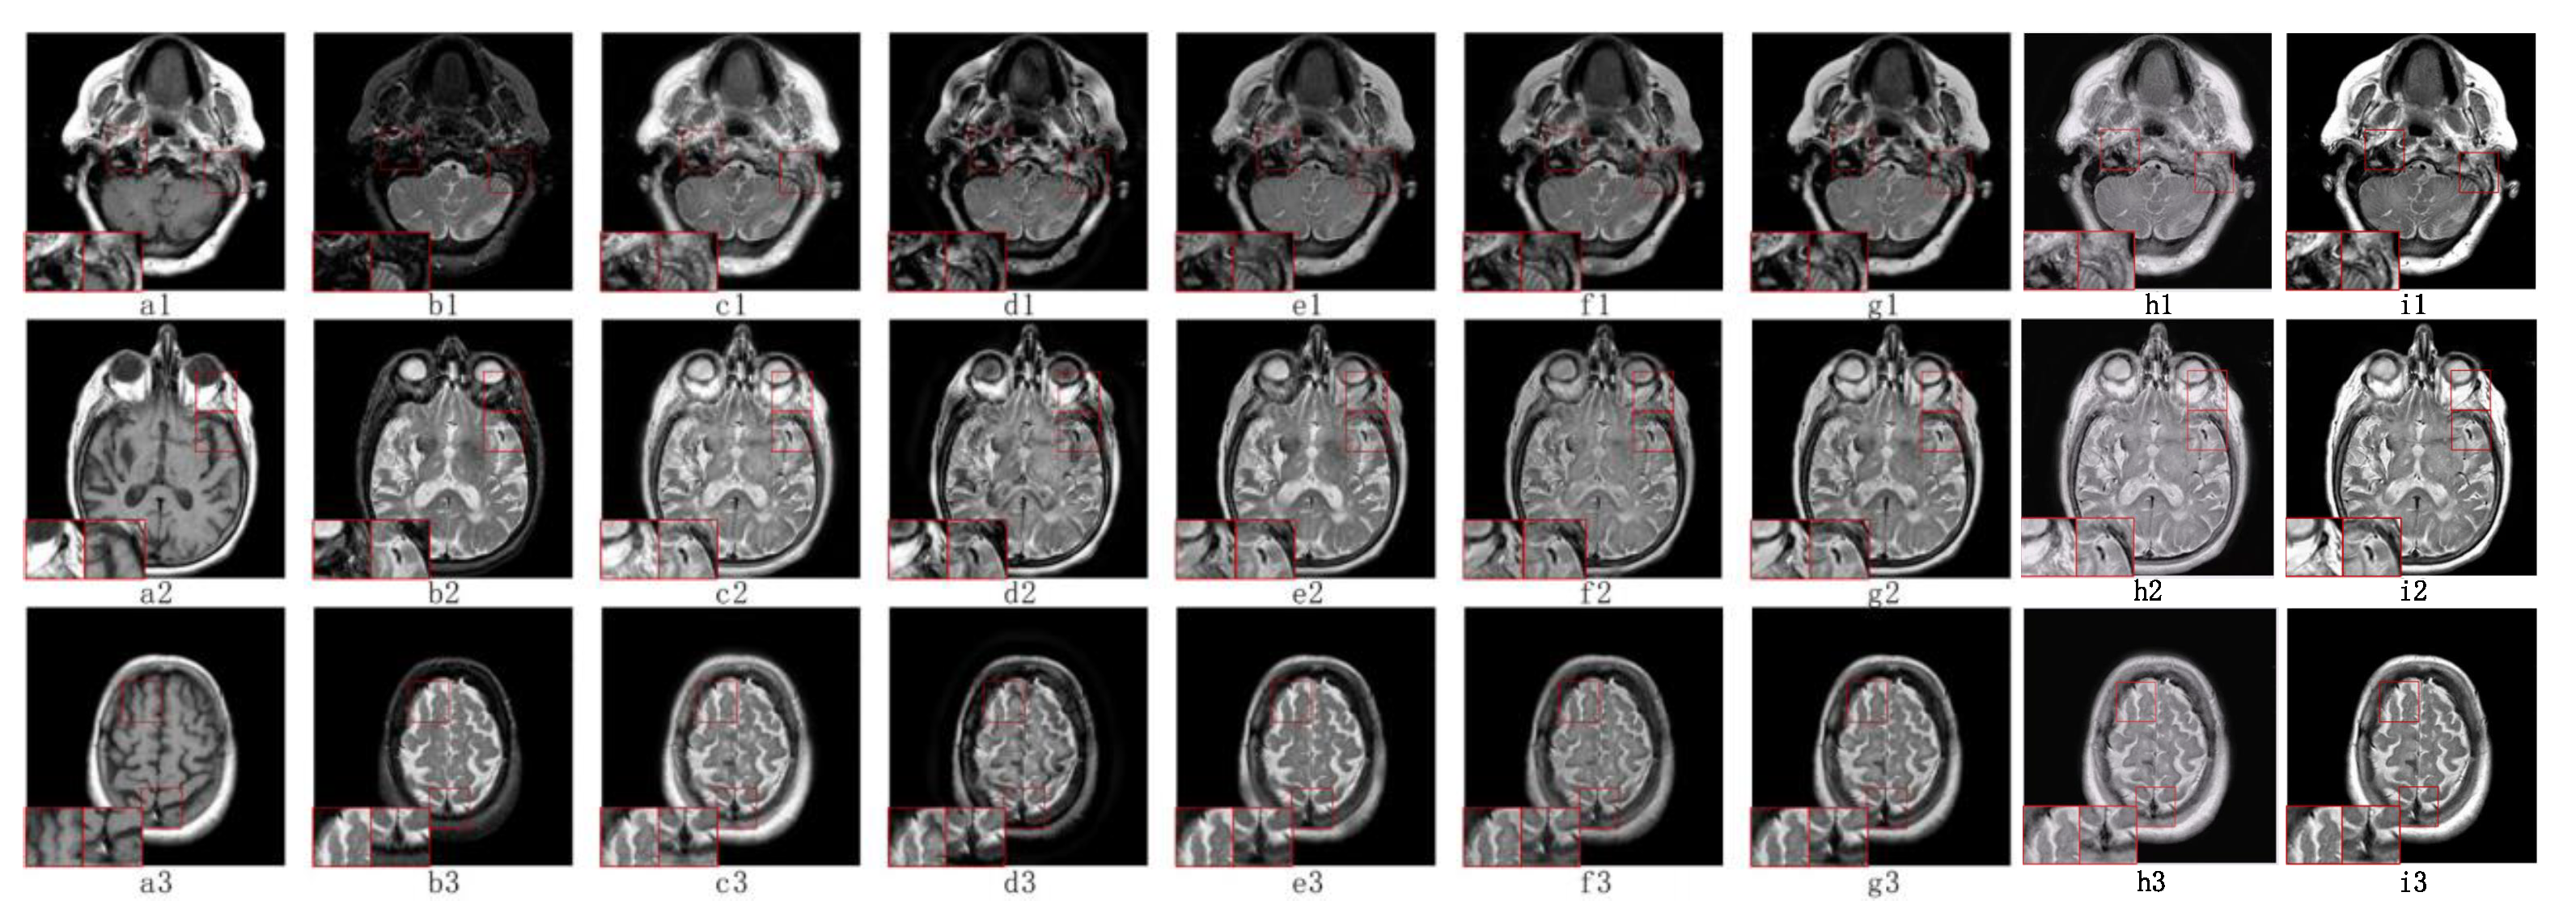

5.2. Visual Effects Analysis

5.2.1. Fusion Analysis on T1-T2

5.2.2. Fusion Analysis on T2-PD

5.2.3. Fusion Analysis on CT-MRI